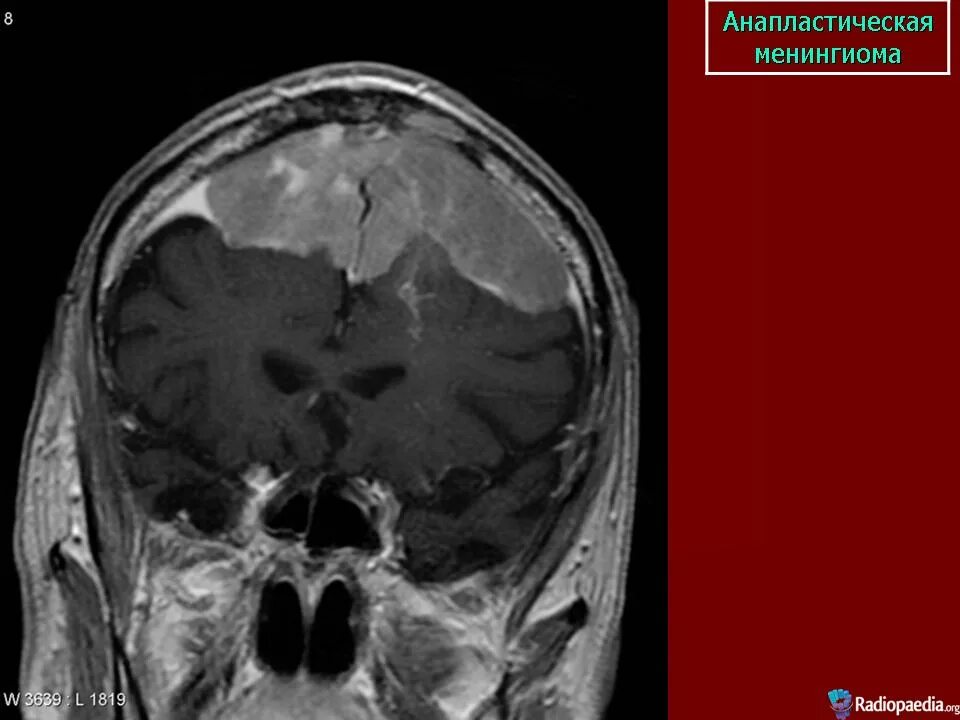

Менингиомы головного мозга мкб